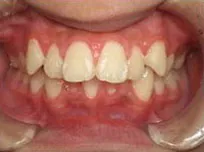

症例1

| 治療期間 | 11ヶ月(2021年6月〜2022年5月) |

| 費用 | 495,000円(税込) |

| リスクや副作用 | 成長期が終わった18歳以降に、2期矯正が必要になることがある |